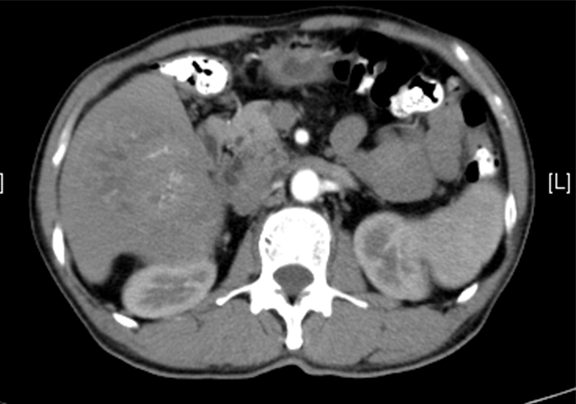

上腹部动态增强CT:1. 肝右叶占位性病变,考虑肝Ca 并肝右静脉瘤栓可能性大,请结合临床2. 副脾3. 肝内外胆管扩张,必要时MRCP检查4. 胰腺颈部小囊状低密度影,建议MRI 检查

术前CT检查:

动脉期

静脉期

平衡期